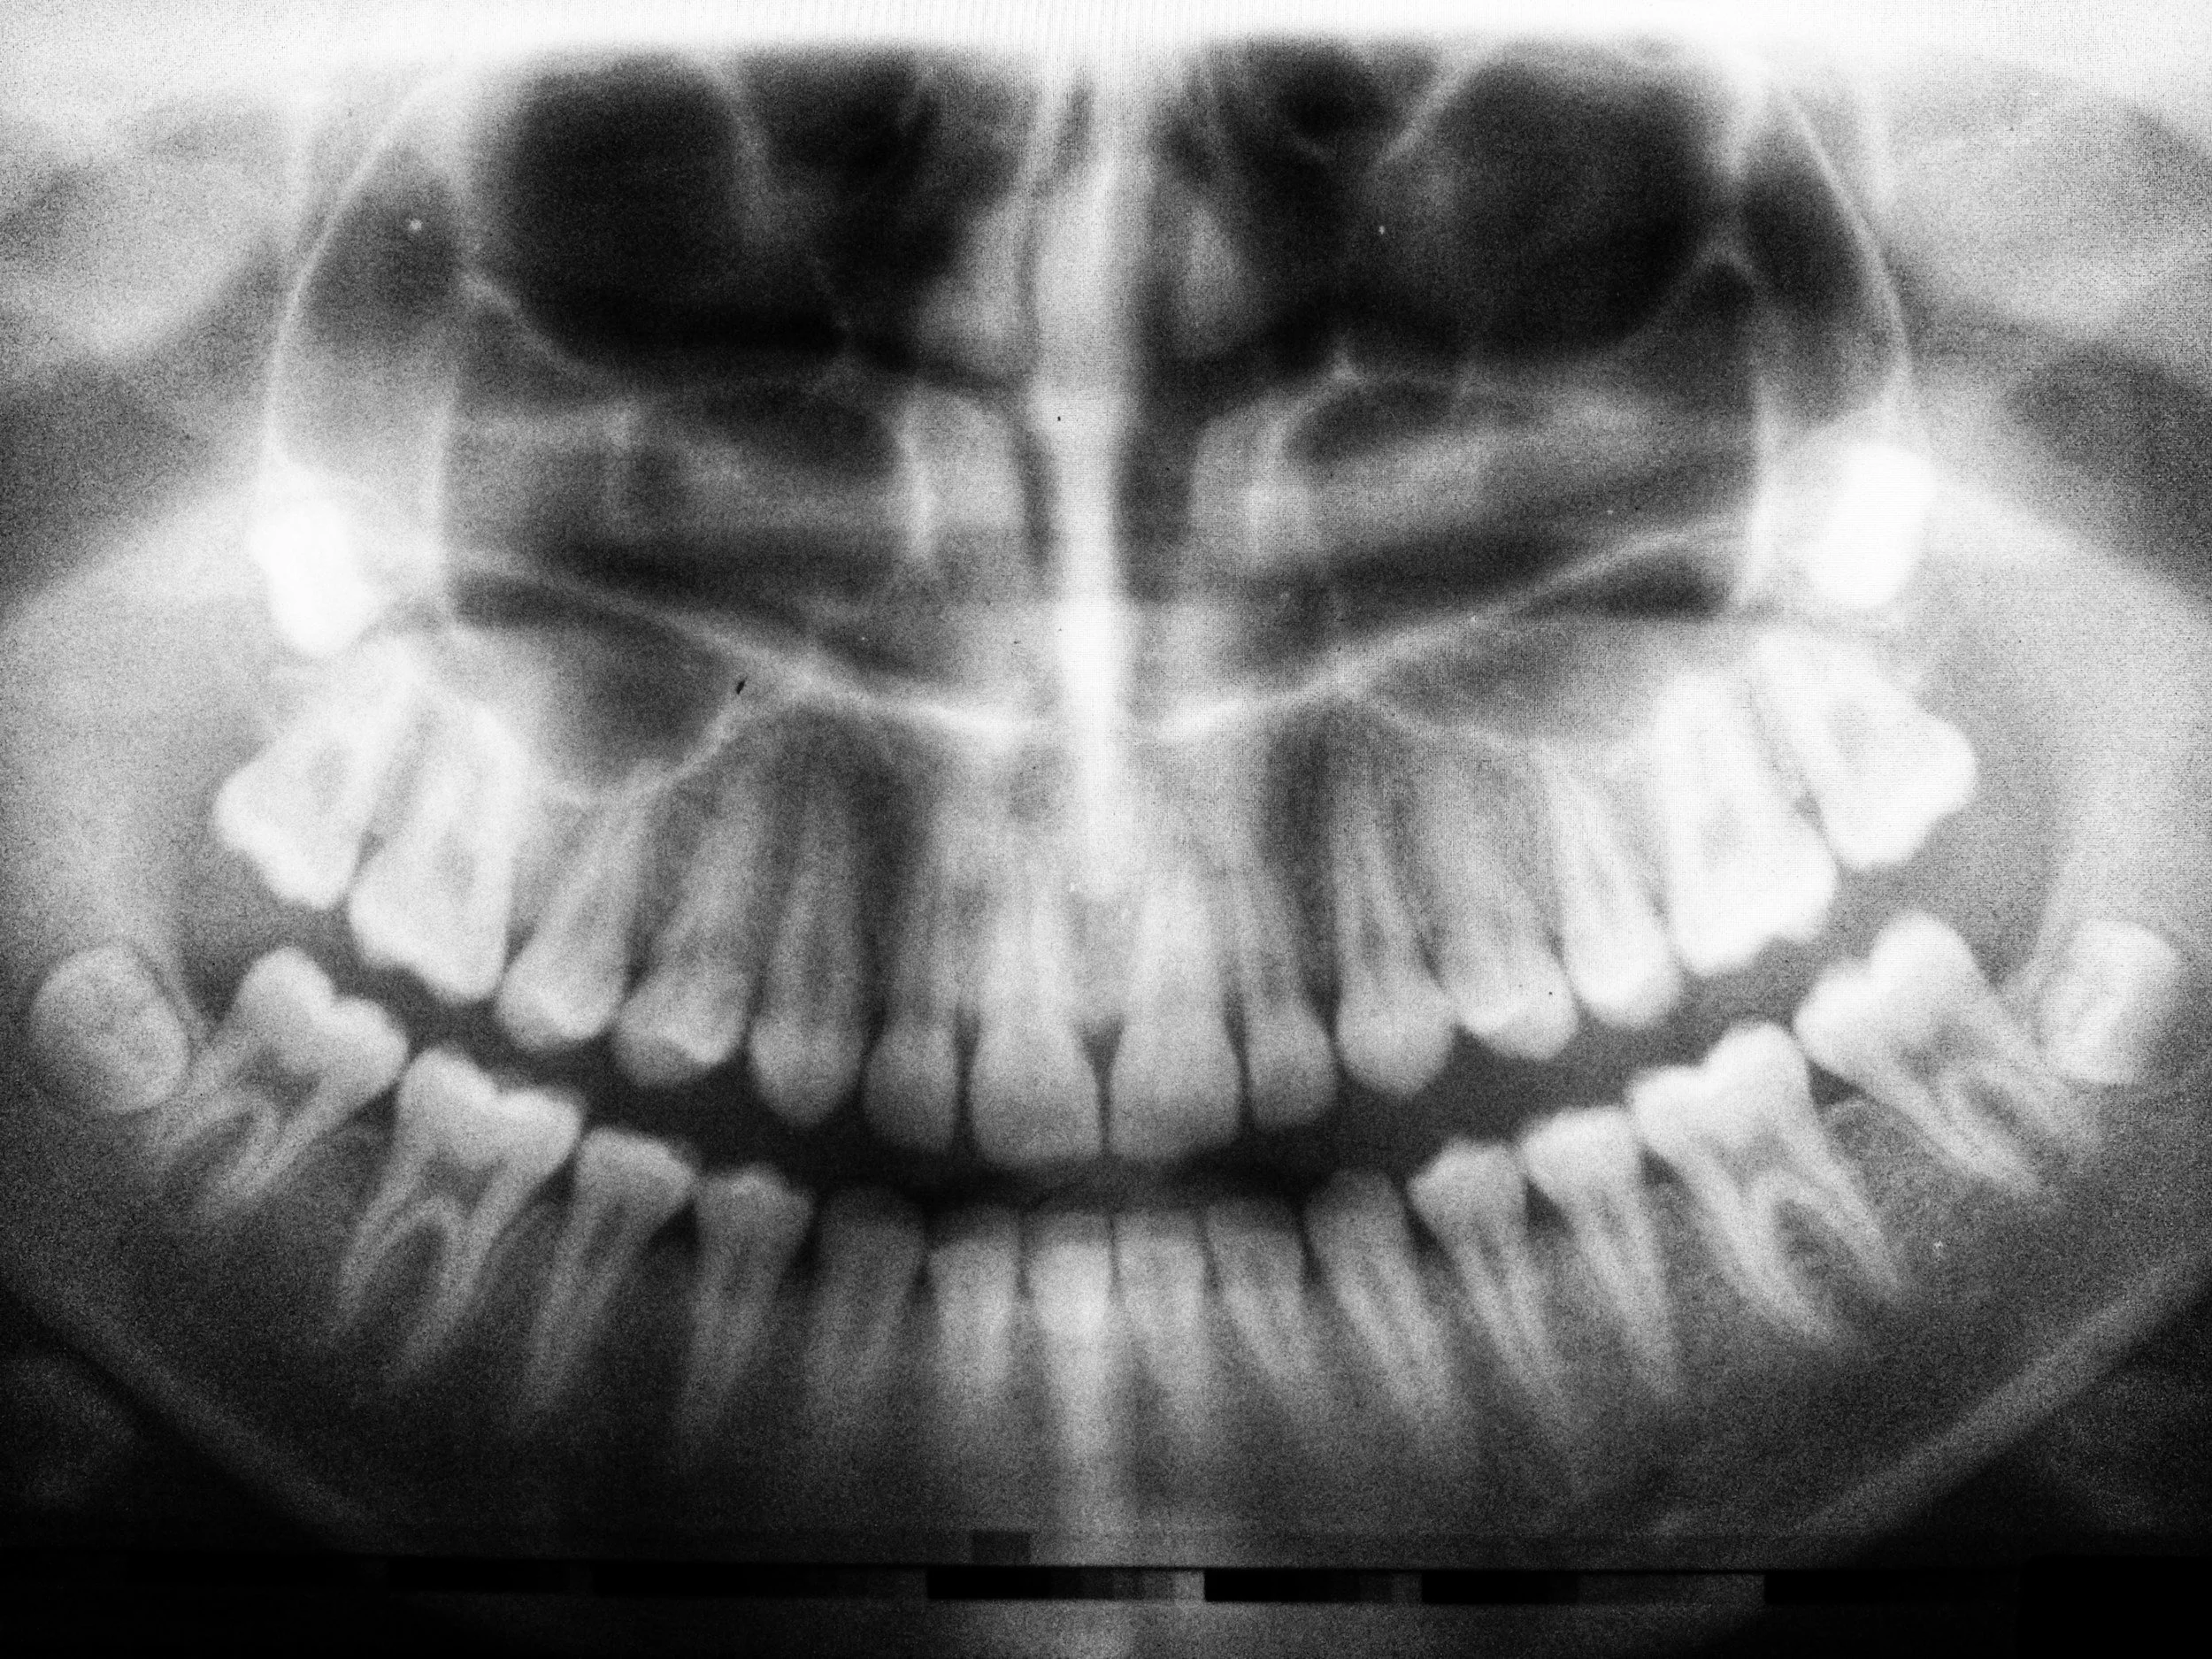

2. Digital X-Rays

We use the latest digital X-ray technology to capture detailed images of your teeth and jaw. These high-resolution images allow us to spot issues that may not be visible during the physical exam, such as hidden decay, bone loss, or impacted teeth. Digital X-rays are safer and use significantly less radiation than traditional X-rays.2.